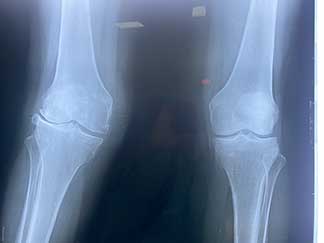

Radiografia AP de ambas rodillas donde se observa deformidad en valgo de rodilla derecha